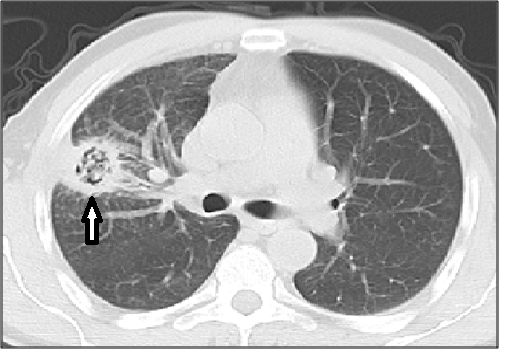

CT扫描显示:(早期IPA)小结节和/或小的胸膜,楔形改变,周围有磨玻璃光晕(晕征)。晕征代表肺泡出血。

随着疾病的进展,结节可能会出现空洞,坏死的薄壁组织会从邻近的肺部分离,形成类似于曲霉菌中所见的空气新月形。

在正确的临床环境中,由磨玻璃晕环绕的结节或实变,进展为空洞或空气新月征,形成被认为是典型的血管侵袭性曲霉菌病。

图13:宫颈癌化疗后子,严重中性粒细胞减少症患者的侵袭性肺曲霉病。MDCT扫描显示双侧多个不明确的结节,伴有外周磨玻璃改变,中叶外侧段的实变区域,也被磨玻璃改变区域包围。